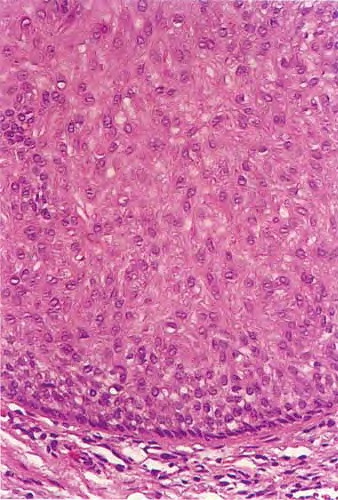

Trichilemmoma =ورم غمد جذر الشعرة